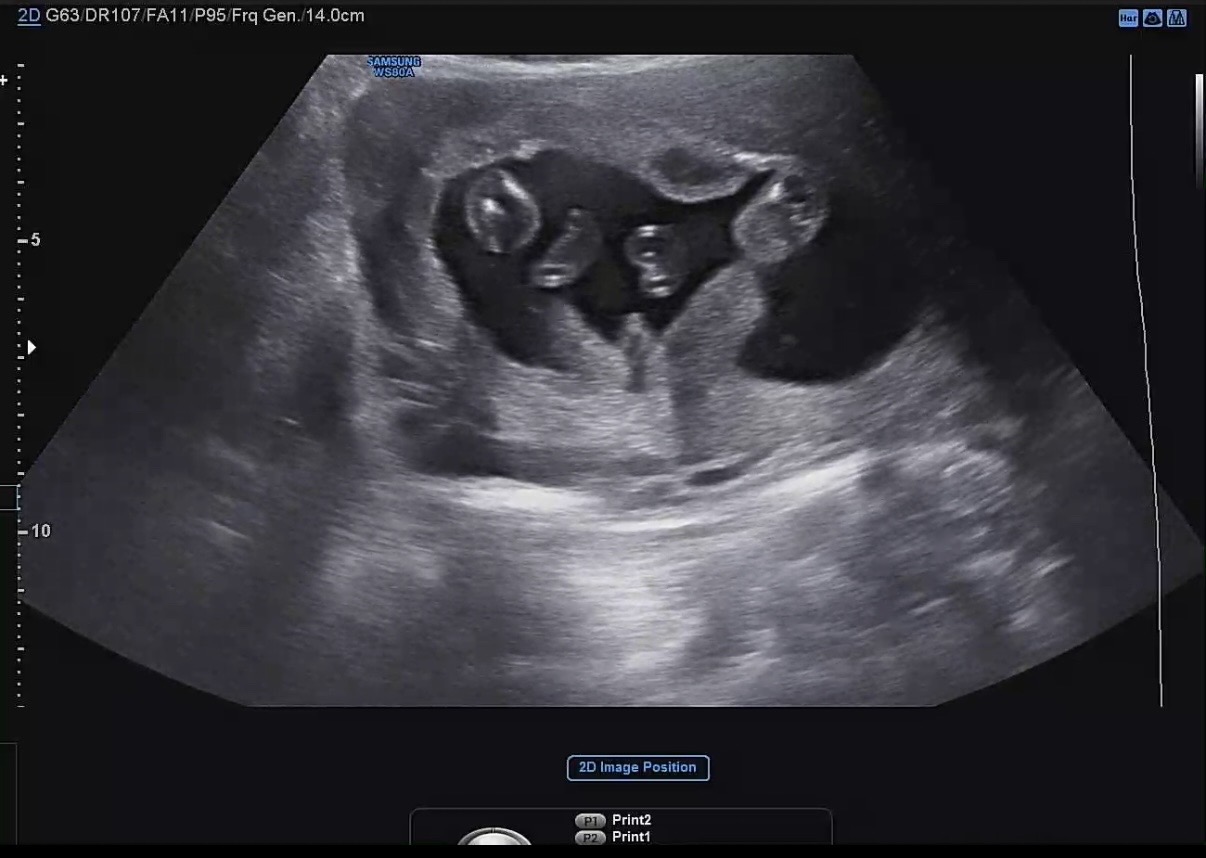

의사쌤이 딸이라는데 춈파가 아들같아요..!

의사쌤은 딸이라는데 최근에본 춈파에서는 뭔가 아들같지않나요ㅠㅠ!? 알려주세여🙏🏻

아근데 다시 다녀왔는데 딸이라네요!!😝

저도 딸인데 엉덩이 뒷라인이 안보일때 보이는건 탯줄! 이더라구요! 이사진도 살짝해매한데 혹시 상황기억 하시나요? 이거 보일때 엉덩이 뒷라인도 확실히 보이셨어요?🥰

고럼 가능성은 2가지네요 1. 고성능초음파기계와 신의 컨트롤로 깊이 더 잘보여 탯줄이 고추처럼 보였다 2. 10년 공부하고 몇년동안 근무경력있는 의사가 고추보이는 순간 멍때렸다🤣